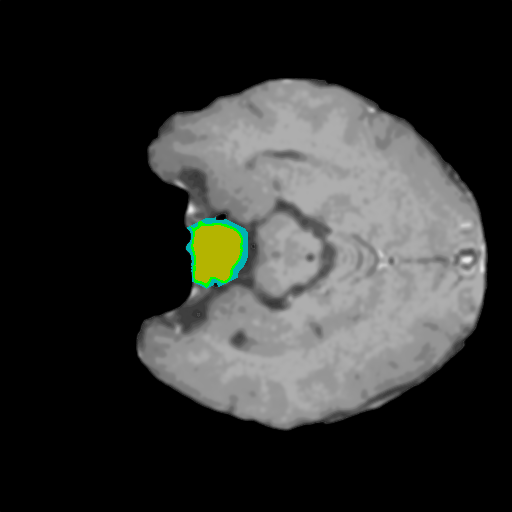

Extensive experiments have been performed in the current setup, and experimental outcomes are reported with the demonstration of numerical and statistical analyses using the proposed QFS-Net, QIS-Net [39], convolutional U-Net [18] and Residual U-Net (URes-Net) architectures [20]. The human expert segmented skull-tripped contrast enhanced DSC brain MR input image slices of size and ROIs are provided in Figure 5 as samples. The demonstration of QFS-Net segmented images followed by the essential post-processed outcome on the slice no. for class level with four distinct activation schemes () are shown in Figure 6. It is evident from the experimental data provided in Table LABEL:tab1 that the proposed QFS-Net performs optimally for the -connected quantum fuzzy pixel information heterogeneity assisted activation () with and gray scale set in comparison with other thresholding schemes and gray scale sets under the four evaluation parameters () [44]. The segmented tumors obtained using the proposed self-supervised procedure under class transition levels with four different thresholding schemes , , and are demonstrated in Figures 7- 8 for the class boundary sets and [39], respectively. The segmented images using the remaining two class boundary sets ( and ) [39] are provided in the supplementary materials section. The segmented ROIs describing the whole tumor region after the masking procedure using QIS-Net, U-Net and URes-Net are also reported in Figure 9.